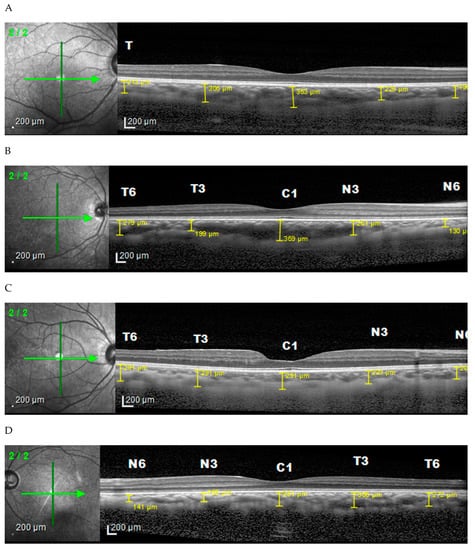

2. Materials and Methods

2.2. Ophthalmology Examination